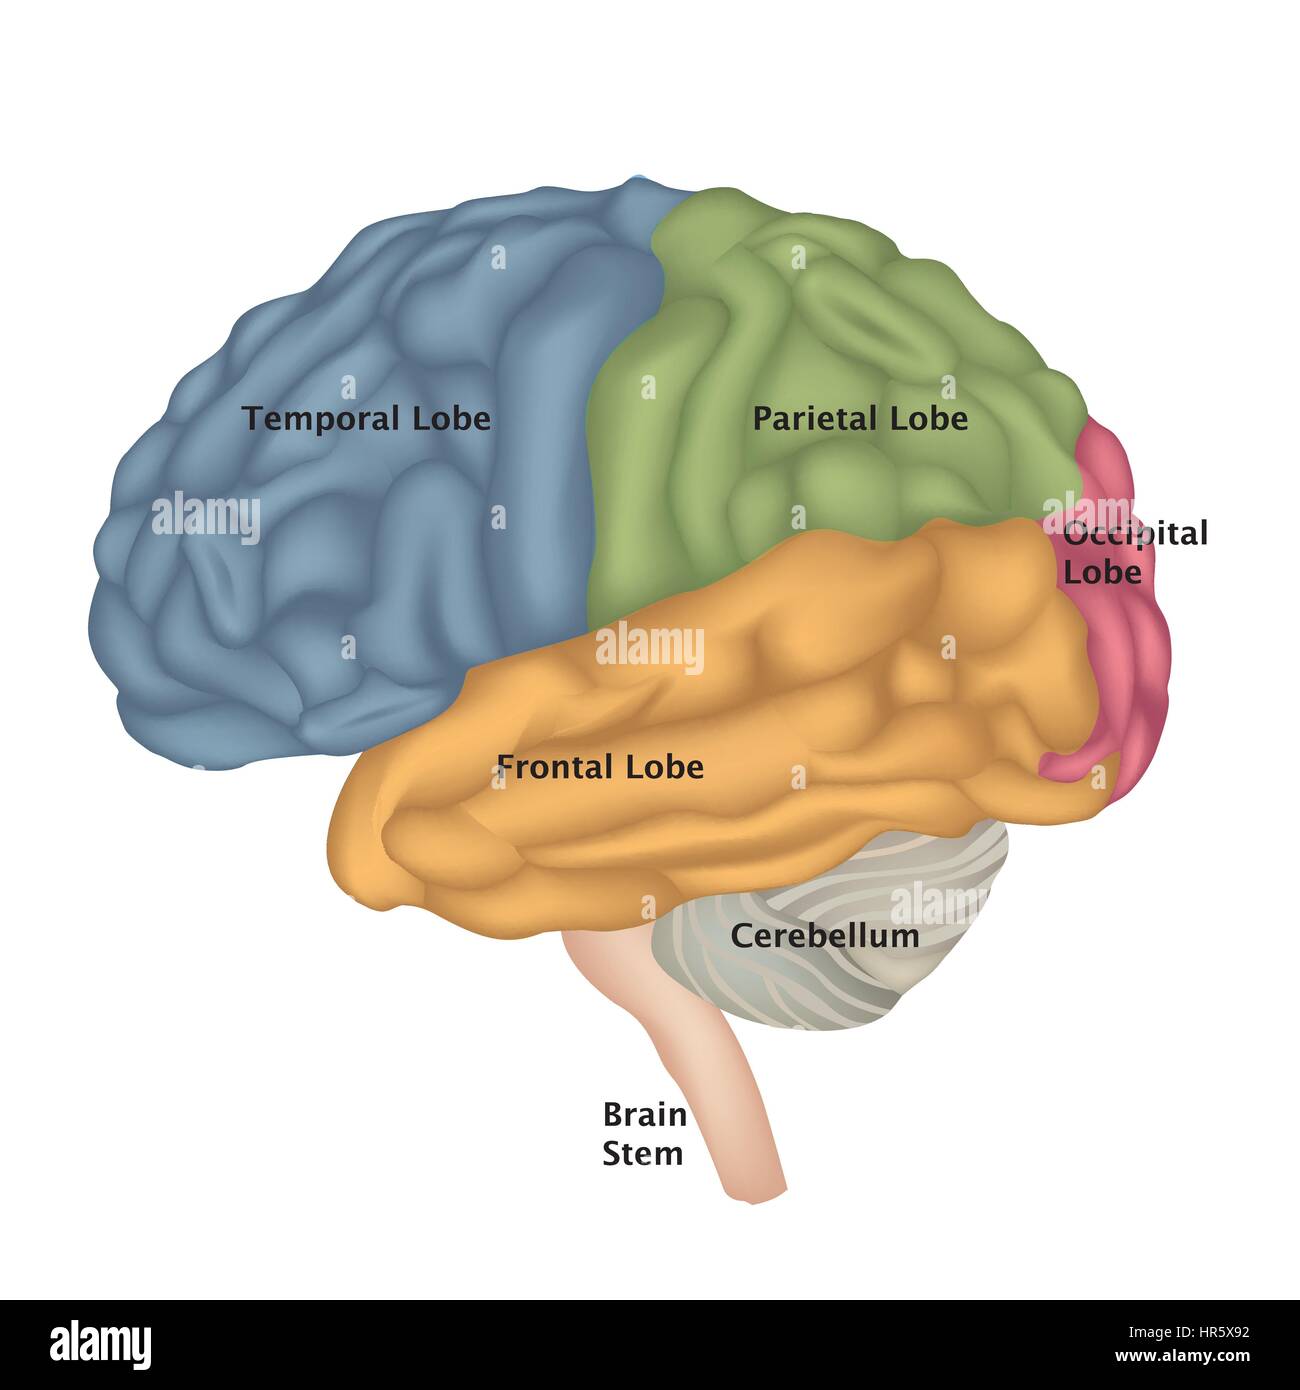

RF2R1KGAT–Struttura cerebrale umana. Emisferi e lobi della corteccia cerebrale. lobi frontali, temporali, occipitali e parietali. vista laterale e superiore

RF2Y8XEWG–Anatomia del cervello umano. Emisferi cerebrali, corteccia cerebrale, frontale, parietale, temporale, lobi occipitali, cervelletto e tronco cerebrale, fessura cerebrale.

RF2E374NN–Struttura dell'illustrazione della corteccia cerebrale. Regioni anatomiche colorate responsabili dell'intelligenza e del movimento.

RF3BJ1K42–Anatomia del cervello umano. Lobi frontali, occipitali, parietali e temporali, cervelletto e tronco cerebrale. Poster dettagliato del vettore